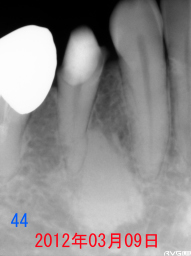

2008年08月18日:初診 44番の隣接面カリエス 主訴:歯がしみる。 下記:同部の拡大 |

|

虫歯(軟化象牙質)が大きく深いので むし歯をすべて除去すると、神経(露髄)する 可能性が大きい。 神経を取らないでいいようにフッ素洗口(NaF) を指示。 目的 第二象牙質の促進と虫歯の回復。 |